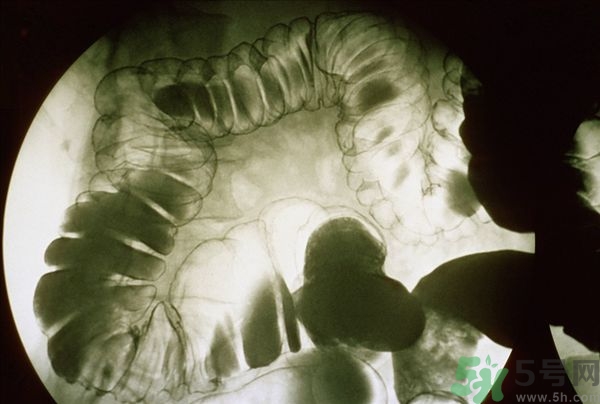

腸炎的分類其實(shí)有很多,比如盲腸炎、潰瘍性大腸炎、慢性腸炎、急性腸炎等等,是比較常發(fā)生的胃腸疾病,當(dāng)我們的腹部出現(xiàn)劇痛的時(shí)候首先我們要確定是哪一種疾病,并且要及時(shí)的進(jìn)行治療,腸炎嚴(yán)重的時(shí)候甚至有休克的可能,下面我們就來說說當(dāng)腸炎患者出一了腹前的時(shí)候應(yīng)該怎么緩解與治療。